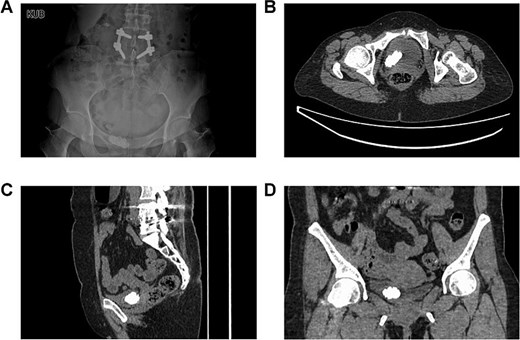

A 48-year-old female was admitted with a diagnosis of “multiple bladder stones” based on color doppler ultrasound (CDU) examination. The patient complained of frequent urination without back pain or fever. Ultrasound revealed no hydronephrosis in both sides. The patient had a history of lumbar surgery and cesarean section. Upon admission, no kidney percussion pain was noted. Blood routine tests, renal, and coagulation function tests were normal. Urinalysis showed leukocytosis, and urine culture was negative. Kidneys, ureters, and bladder (KUB) imaging reported a stone in the pelvic area (Fig. 1A). Computed tomography scan (CT) reported a large 4 cm “bladder stone” and multiple stones in the right kidney (Fig. 1B–D).

The preoperative imaging examinations of the patient. (A) The plain film of kidney–ureter–bladder. (B–D) Computed tomography.